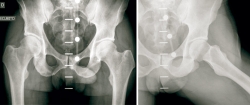

Presentamos el caso de un varón de 48 años, instructor de tenis profesional, sin antecedentes clínicos relevantes. Consulta por coxalgia izquierda incapacitante durante la actividad laboral de unos 18 meses de duración. El examen físico mostró dolor en flexión y rotación interna de la cadera izquierda y una prueba de choque positiva. Se realizaron radiografías para evaluar la presencia de morfologías que pudieran predisponer a un pinzamiento femoroacetabular (Figura 1). No se observó morfología anormal o signos de osteoartritis. El tratamiento inicial incluyó la prescripción de antiinflamatorios no esteroideos (AINE) y la modificación de la actividad física. Se realizó una resonancia magnética (RM) para completar el estudio. Los resultados de la RM no identificaron alteraciones morfológicas o cambios de señal en la cabeza femoral que pudieran sugerir necrosis ósea, focos de osteocondritis, fracturas por estrés, edema óseo u osteoporosis transitoria. Se identificó una lesión del labrum anterior con un quiste paralabral asociado a esta, de 32 × 17 mm (Figura 2). Después de 3 meses de tratamiento conservador sin mejoría clínica, se propuso la escisión quirúrgica y la reparación del labrum. La extirpación quirúrgica se realizó a través de artroscopia mediante técnica fuera-dentro. Todas las estructuras óseas en el compartimento central no mostraron signos patológicos. Se observó una lesión del labrum en su zona anterosuperior (zona 2)(2). En el compartimento periférico, se identificó una gran lesión quística que rodeaba el borde anterosuperior del labrum y el acetábulo (Figura 3). La extirpación completa del quiste se realizó artroscópicamente utilizando material específico para la artroscopia de cadera. No se registraron complicaciones intraoperatorias. La reparación labral se realizó con un sistema de anclaje All-Suture® de tipo Y-Knot® (Conmed). Se inició el protocolo de fisioterapia postoperatoria habitual de nuestro centro, permitiendo la carga parcial con dos muletas al momento del alta con progresión gradual a peso completo en un periodo de 2-3 semanas, seguido de un protocolo de rehabilitación para conseguir el rango completo de movilidad articular y lograr la fuerza completa de la extremidad. En un periodo de 3 meses, el paciente regresó por completo a la actividad física. No se observaron complicaciones.

Figura 2. A: imagen coronal de STIR que muestra la lesión quística (flecha roja) que ocupa el músculo psoas; B: desgarro labral (flecha amarilla); C: imagen axial T2 que compara ambas caderas. La lesión quística (flecha roja) se identifica en el espacio articular anterior de la cadera izquierda; D: T2 imagen sagital del quiste labral (flecha roja) inferior a la espina iliaca anteroinferior.